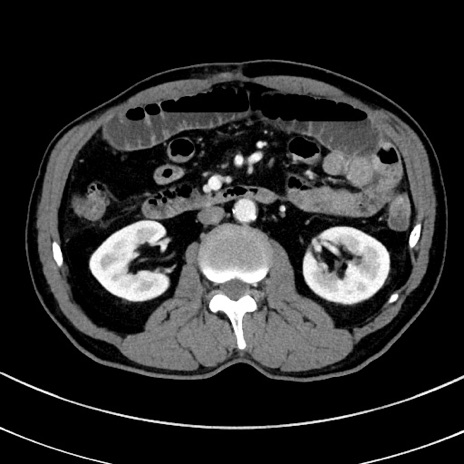

冠状断像

【症例】 60歳代男性

【主訴】 黒色吐物

【現病歴】 4日前から嘔気自覚、2日前の朝食後にも嘔気あり、自分で手で嘔吐反射起こし嘔吐したところ血が混ざっていたため受診。

【既往歴】 5年前汎発性腹膜炎を伴う急性虫垂炎で手術、高血圧、前立腺肥大症、高脂血症

【身体所見】 腹部正中に手術癩痕あり 腹部平坦・軟圧痛なし膨満感あり

【データ】WBC 8400、CRP 4.54